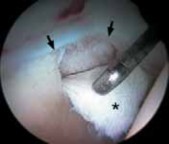

1. Most symptomatic labral tears are managed with selective débridement of the damaged portion ( TECH FIG 1).

A complete joint survey is performed with thorough inspection and palpation of the labrum, identifying its damaged portion.

Most labral resection is carried out with a power shaver, debulking the damaged tissue.

Hand instruments and an arthroscopic knife may aid in this resection.

It is important to preserve the healthy tissue but create a stable transition zone when completing the débridement.

A radiofrequency device is especially useful for this because of the limited maneuverability imposed by the architecture of the joint.

Diseased tissue has an increased water content and responds selectively to the thermal device.

TECHNIQUES A B TECH FIG 1 • Arthroscopic view of a right hip from the anterior portal. A. A fragmented labral tear with degeneration within its substance is identified. B. Débridement is initiated with the power shaver. C. A portion of the comminuted labral tear is conservatively stabilized with a radiofrequency probe. D. The damaged portion has been removed, preserving the healthy substance of the C D labrum. LABRAL REPAIR